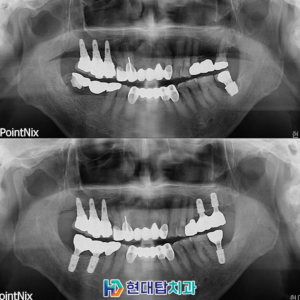

울산동구임플란트 정밀한 진단을 바탕으로 ​ 치아가 건강한 것만으로도 건강한 노후를 준비할 수 있습니다. ​ 그만큼 치아는 꼼꼼하고 세심한 건강관리가 필요한 부위 중 한 곳인데요. ​ 단순히 음식물을 섭취하여 저작하는 기능 외에도 인상을 좌우하는 역할과 명확한 발음을 구사할 수 있도록 합니다. ​ 이렇듯 치아는 전신 건강과의 연관성 등 우리의 삶에 있어 더보기…

울산동구치과 망설이고 있다면 임플란트의 정의 실제 임플란트 사례 상악동 & 의식하 진정 임플란트란 의료진 소개 치아 건강은 백세 시대 속에서 삶의 질을 결정하는 핵심 요소입니다. ​ 치아는 음식물을 저작하고 부수는 저작활동을 하면서 원활한 소화가 이루어질 수 있도록 도움을 줍니다. ​ 하지만 한번 손상되거나 상실된 치아는 회복이 불가능하기 때문에 정기적인 치과검진과 더보기…

울산동구임플란트 잘하는곳 어디로 가야 할까   세월이 흘러갈수록 신체는 기능이 약해지고 여러 가지 질환이 발생합니다. ​ 치아 역시 예외는 아니며, 노화로 인해 치아가 흔들리거나 빠지게 되는 경우가 있는데요. ​ 이러한 원인으로 인해 치아를 상실하게 되면 생각보다 많은 불편함을 가져오게 됩니다. ​ 저작기능이 저하되어 소화에 문제가 발생하고, 올바른 발음을 구사하기 힘들어지는 더보기…